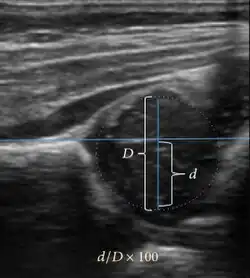

Ultrasound

Ultrasound is the first-choice technique for diagnosis of newborns hip dysplasia. In experienced hands with appropriate technology, ultrasound can also be useful during the first year of life. Some European healthcare systems encourage universal ultrasound screening in neonates between the sixth and eighth weeks. Although it shows higher initial costs caused, it leads to significant reduction in the total number and overall costs of dysplastic hips undergoing operative and nonoperative treatment.[1]

Ultrasound allows categorizing pediatric hips, according to Graf’s criteria, in four main types: normal, immature, and dysplastic (subluxed and dislocated). This classification is based on measurements of the acetabular inclination angle (alpha), cartilage roof angle (beta), and infant age. The femoral head coverage can also be determined by dividing the length of the femoral head covered by the acetabular fossa and the diameter of the femoral head. Its lower normal limits are 47% for boys and 44% for girls (Figure 11).[1]

Figure 11:

-

Useful ultrasound measures in neonatal hip sonography, alpha and beta angles.[1] -

Measurement of femoral head coverage.[1]